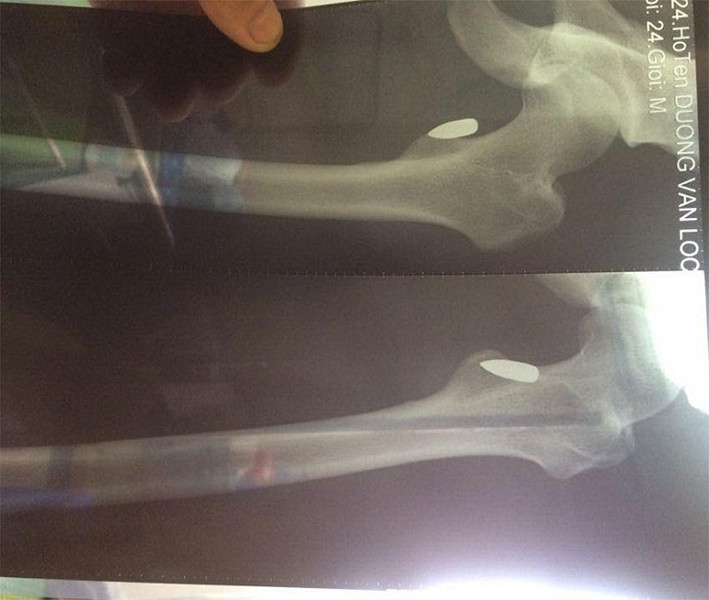

Trao đổi với phóng viên, anh Lộc cho biết: "Đến khi vào bệnh viện cấp cứu, chụp X - quang, tôi mới biết đùi mình bị trúng một viên đạn. Rất may là đầu đạn chỉ đi vào phần mềm, cách xương vài milimét. Thực sự, tôi cũng không biết viên đạn bay từ đâu đến".

Hình ảnh viên đạn găm trúng đùi VĐV võ thuật Dương Văn Lộc

Mặc dù vậy, do vết thương phức tạp, nạn nhân đã được chuyển xuống Bệnh viện Bạch Mai. Sau đó, tiếp tục sang Bệnh viện Việt Đức để tiếp tục xử lý vết thương, gắp đầu đạn ra ngoài.

Anh Lộc thông tin, hiện viên đạn vẫn đang nằm ở bên trong chân, các bác sĩ chưa thể mổ để gắp đầu đạn, vì tổn thương do đạn bắn gây ra khá nghiêm trọng, đầu đạn nằm sâu, gần xương nên chưa thể can thiệp.